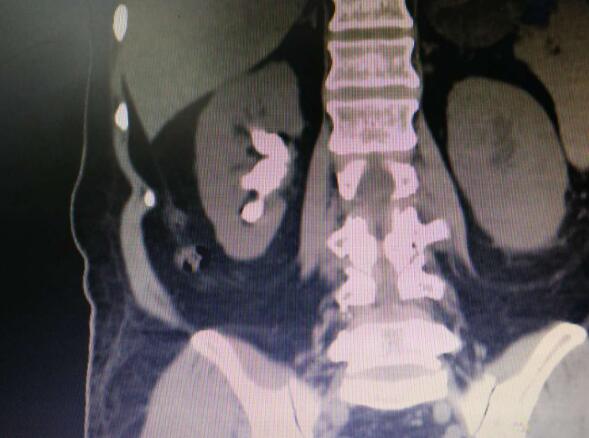

清远丘伯年近70岁,原来自觉身体各方面都不错,就是近2个月以来经常出现右侧腰部酸胀不适,同时还有心砰砰乱跳的感觉。于是在子女的陪同下到医院检查。经过初步的检查,医生发现老人家有2个大问题:1.右边肾脏有个很大的铸型结石堵在肾盂出口处,肾脏开始有点积水感染了;2.心电图提示有心肌缺血,心律不齐,心电传导阻滞III°等等。

通过显示器可见,整个肾盂肾盏都充满了黄褐色的结石。卓主任插入碎石光纤,随着机器的运转,结石在激光的粉碎下一点点崩塌下来并被吸走。而那些稍微大点的石头还争先恐后的挤到镜头前面来。经过2个多小时的努力,丘伯肾脏内的大结石就灰飞烟灭,并统统被吸到一个负压瓶里。既没出血,也没有延误影响视野。

术后麻醉清醒,阿伯就可以自行下地走动。术后第二天就像没事的人出院回家。出院前复查片子发现结石已经消失无踪。卓育敏介绍,由于这个技术刚刚开展,为了安全起见,让患者住院观察一晚。再积累一些病例,经验丰富后应该可以实现当天出院,真正做到日间手术。与传统手术相比,日间手术不仅大大缩短了住院时间,还降低患者住院费用,免去患者家属在病房陪护的不便,最为重要的是,高龄患者将不再成为泌尿外科手术的禁区。